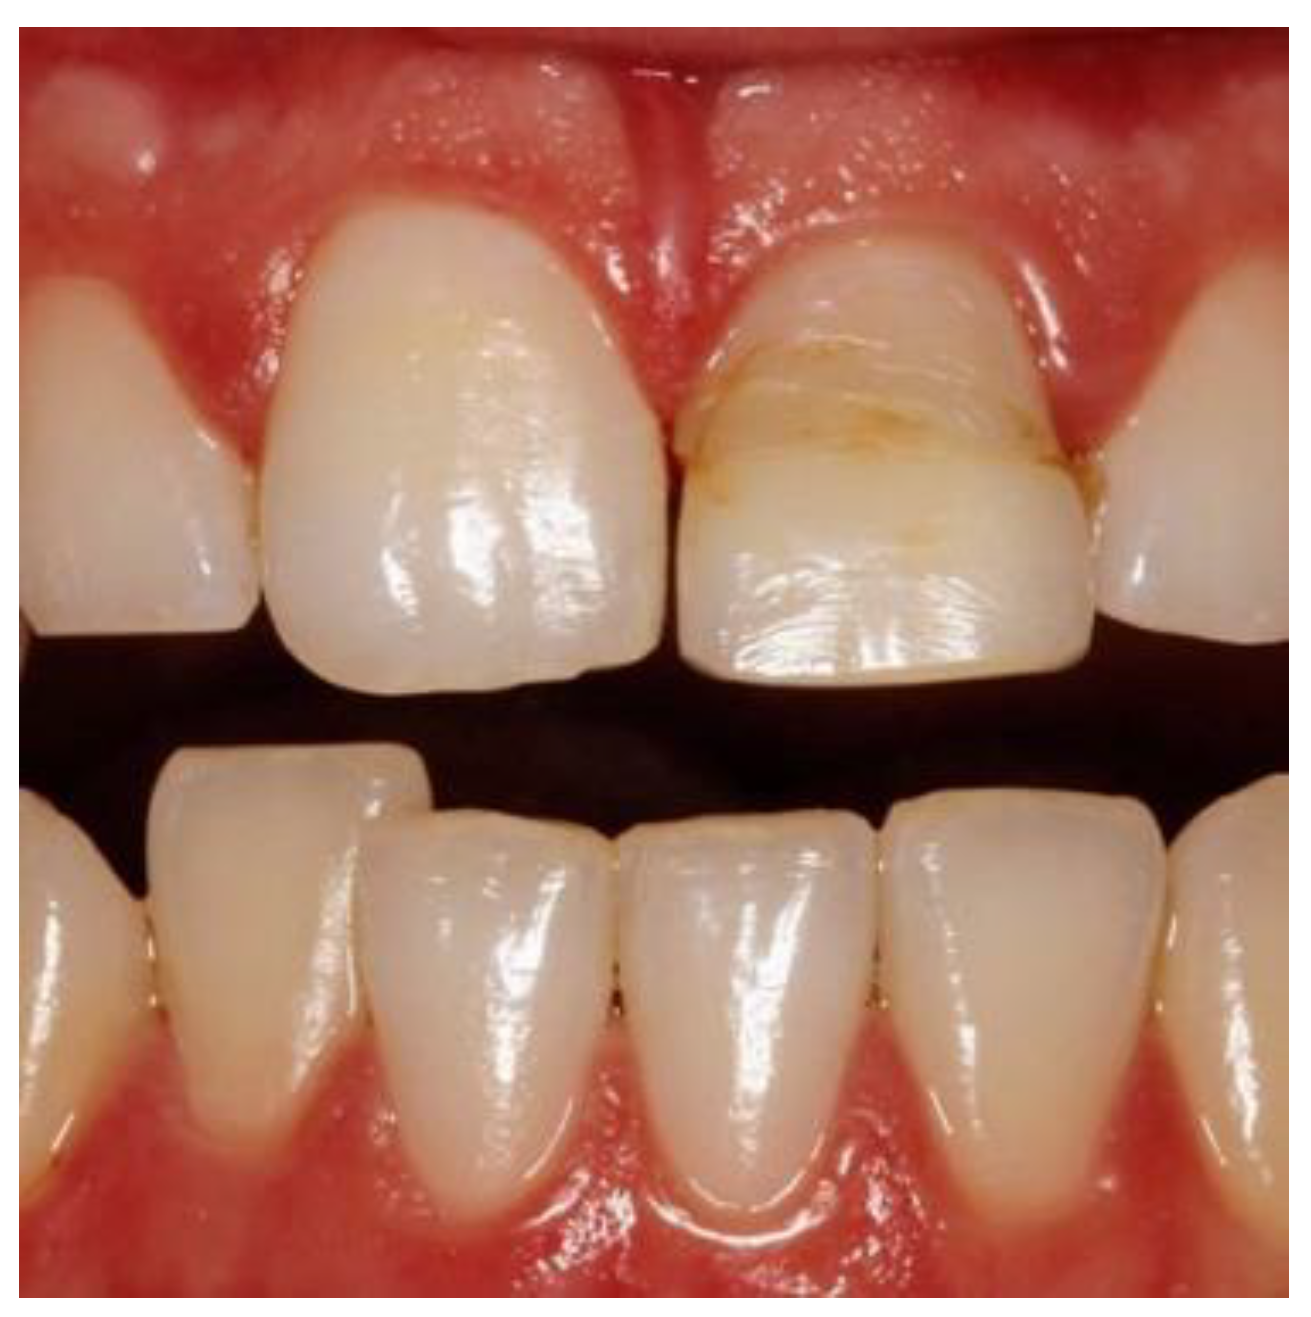

Figure 9. Postoperative image used for PES evaluation.

Preprints 86078 g008